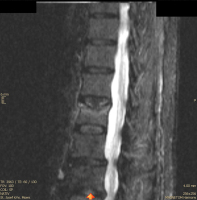

Möglichkeiten der direkten Zementinjektionstechnik bei Wirbelkörperfrakturen - Drei Fallbeschreibungen der Radiofrequenz-Kyphoplastie (RFK) mit ultrahochvikösem Knochenzement